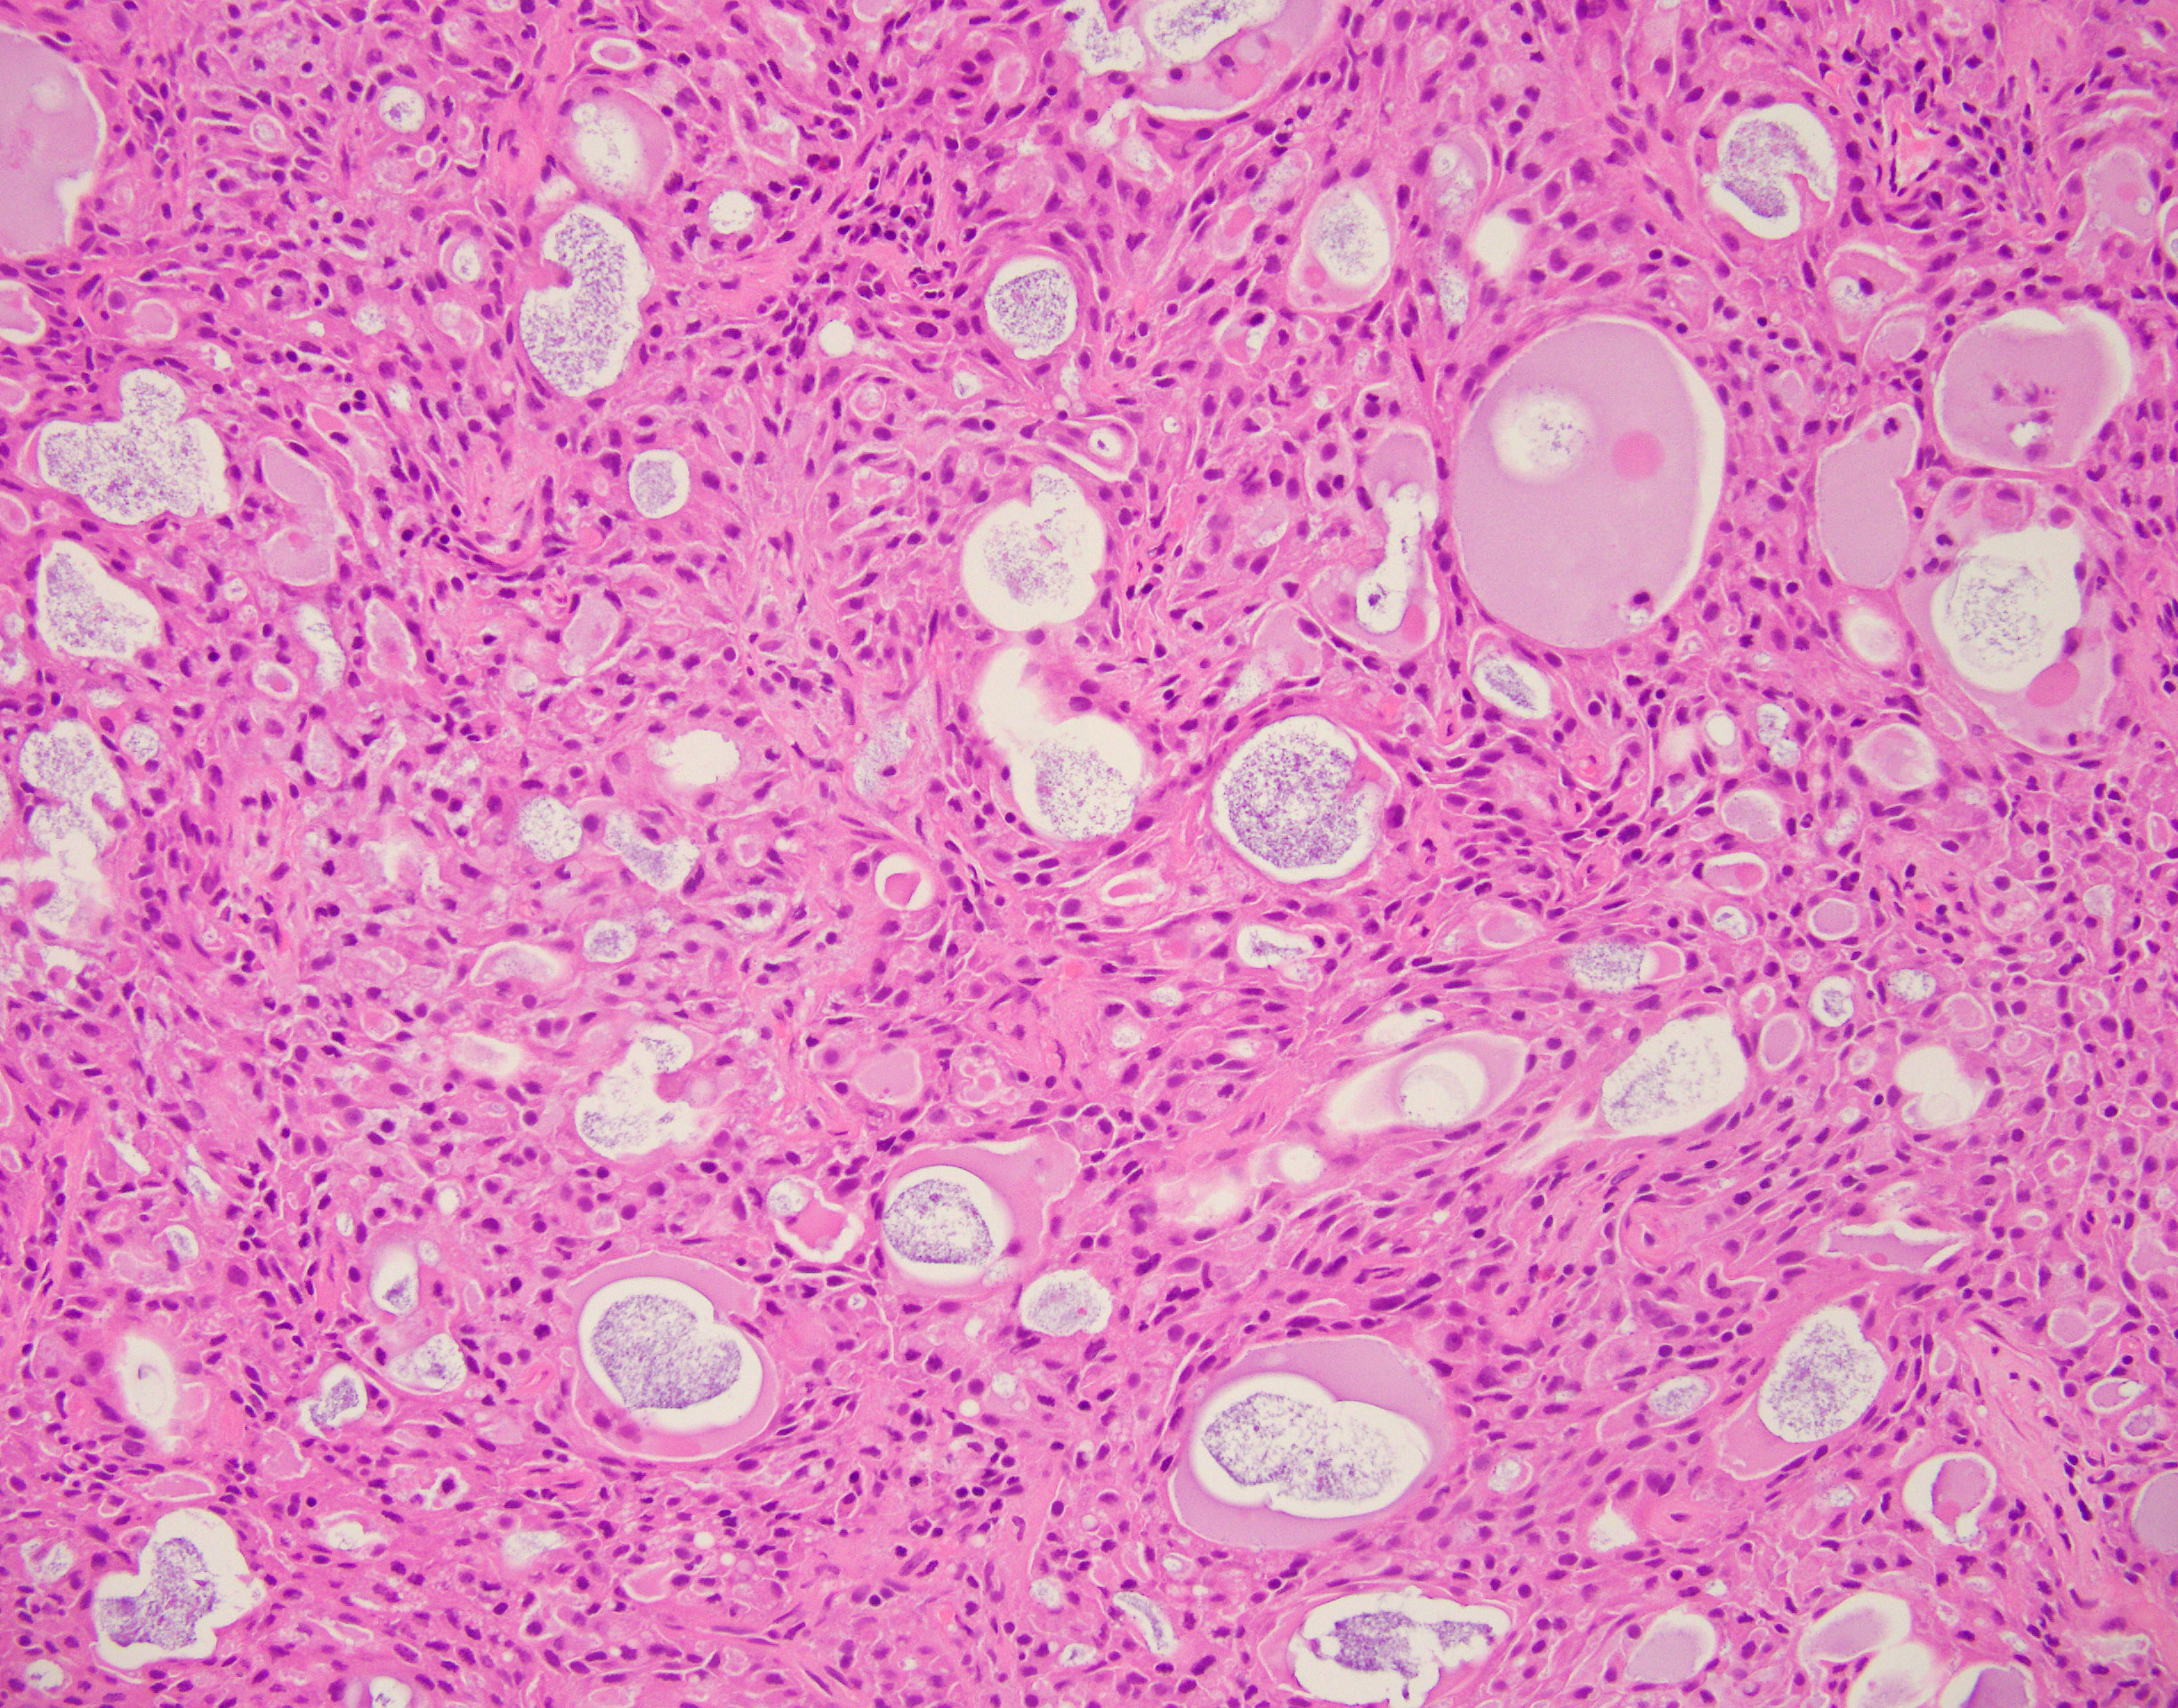

51-year-old male with a three-week history of 2.5 cm left parotid mass. H&E and IHC are illustrated. P63 and DOG1 were negative.

Secretory carcinoma/mammary analogue secretory carcinoma (MASC) is a salivary gland carcinoma with histologic features and molecular changes similar to mammary secretory carcinoma. MASC typically presents as a painless slowly growing parotid mass in a middle age patient with equal sex distribution. Histologically, MASC shows a lobulated or infiltrative lesion composed of cystic, papillary, or tubular structures with luminal secretions. The tumor cells typically exhibit small uniform nuclei with eosinophilic cytoplasm. The differential diagnosis includes acinic cell carcinoma that exhibits PASD positive zymogen cytoplasmic granules, mucoepidermoid carcinoma (MEC) composed of a mixer of cells including intermediate and mucin producing cells and adenoid cystic carcinoma that shows cribriform, tubular, and/or solid with small to medium cells with eosinophilic to clear cytoplasm. MASC is mammaglobin (+), S100 (+), DOG1(-), and p63 (-). Whereas Acinic cell carcinoma is mammaglobin (-) and DOG1(+), Mucoepidermoid carcinoma is p63 and CK5/6 (+), and Adenoid cystic carcinoma is p63 (+) and mammaglobin (-). MASC harbors ETV6-NTRK3 fusion gene resulted from t(12;15)(p13;q25) which has not been detected in other salivary gland neoplasms. MASC is usually indolent tumor, however, lymph node and distant metastases have been reported. Poor prognostic factors include high-grade transformation and high clinical stage at presentation.